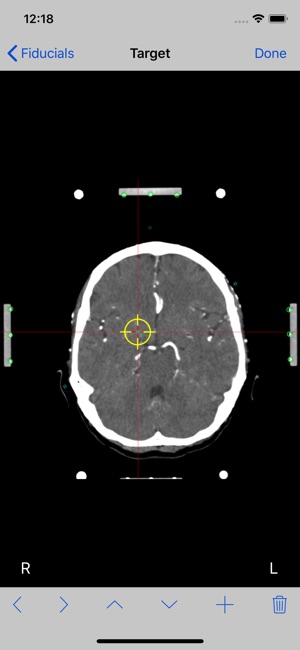

7. Mark each fiducial on the image. StereoCheckRM use nine (9) fiducials. Tap the Done button.

8. Mark the target point you want to reach and tap the Done button.

10.At this point the stereotactic parameters NT, SW, HW, NS and NV will be computed and displayed.